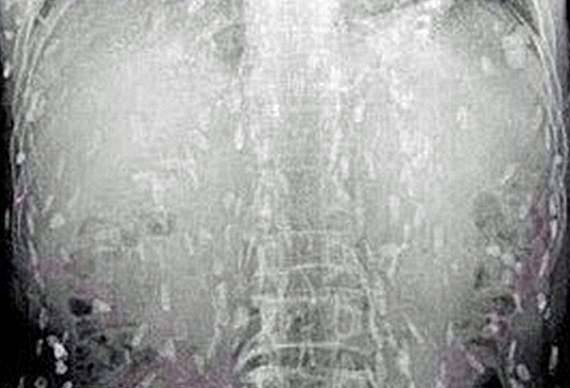

▼这张X光片中的景象可说是让人看的头皮直发麻!据称,这是一名中国男子在吃了生鱼片后全身发痒,到医院求诊后所拍下的,全身上下到处都是「白点」,成群条虫游走全身,光是想像就让人头皮发麻。